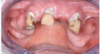

Prothèse Adjointe Complète

Prothèse fixe : Inlay / Onlay